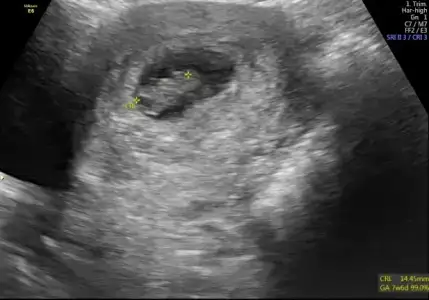

Bebegin Kesedeki Konumuna Göre Cinsiyet Tahmini

Kızlar nette bu resmi gördüm. Cinsiyeti belli olanlar ilk haftalardaki ultrason resimlerinizle uyuyo mu bu resimdekiler

Kizlar Havalianne__ Havalianne__ bana da yorum yaparmisiniz ilki 6+4 haftalik

2cide ise 10+6 görüntüde altta da yaziyor. Her ikiside karindan bu arada